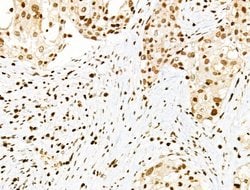

Invitrogen™ Phospho-PDX1 (Ser66) Polyclonal Antibody

Antibody detects endogenous levels of PDX1 only when phosphorylated at Ser66.

| Immunohistochemistry (Paraffin), Western Blot, Immunocytochemistry | |

| Human, Mouse, Rat | |